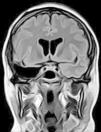

Para ello presentamos dos casos de pacientes mujeres de 50 y 42 años con crisis desde la infancia y diagnosticadas de esclerosis temporal mesial. Ambas fueron intervenidas por nosotros en el año 2000 mediante amigdalohipocampectomía con resección parcial amigdalar más lobectomía temporal izquierda y derecha respectivamente. Las dos pacientes no presentaron nuevas crisis parciales complejas durante los primeros 6 años, empeorando posteriormente por lo que fueron reintervenidas para monitorización con electrodos subdurales y profundos. En ambas se evidenció un inicio ictal compatible con el electrodo situado en la amígdala. La subsiguiente resección del tejido donde se situó el electrodo amigdalar dejó a las dos pacientes libres de crisis.

En estas dos pacientes fue preciso completar la resección amigdalar para conseguir que quedaran libres de crisis. La resección amigdalar es parte importante de la técnica quirúrgica en la epilepsia temporal mesial. Es posible que la amígdala tenga un papel mucho más relevante de lo actualmente considerado en el origen de las crisis.

Two patients are presented who were 50 and 42 years old at the time of surgery. They suffered from seizures since childhood and were diagnosed with mesial temporal sclerosis. A temporal lobectomy with hippocampectomy and partial amygdalectomy was performed on both patients in the year 2000, with one patient operated on the right side and the other one on the left side. Both patients were seizure free after surgery for 6 years, but presented again with seizures after that time. They were evaluated again for surgery, and subdural grids were placed, together with a deep electrode in the remnants of the amygdala. The amygdalar electrode showed to be the seizure onset in the two cases, and its resection rendered both patients seizure free.

These two patients show that a complete amygdalar resection is necessary to render some patients seizure free. It might be the amygdala has a greater role than previously thought.